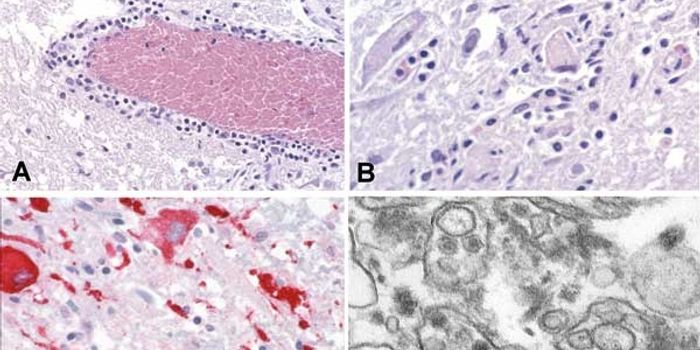

DEC 10, 2018Health & MedicineSarcoidosis is characterized by an exaggerated immune response to an unrecognized antigen, which has not yet been ...